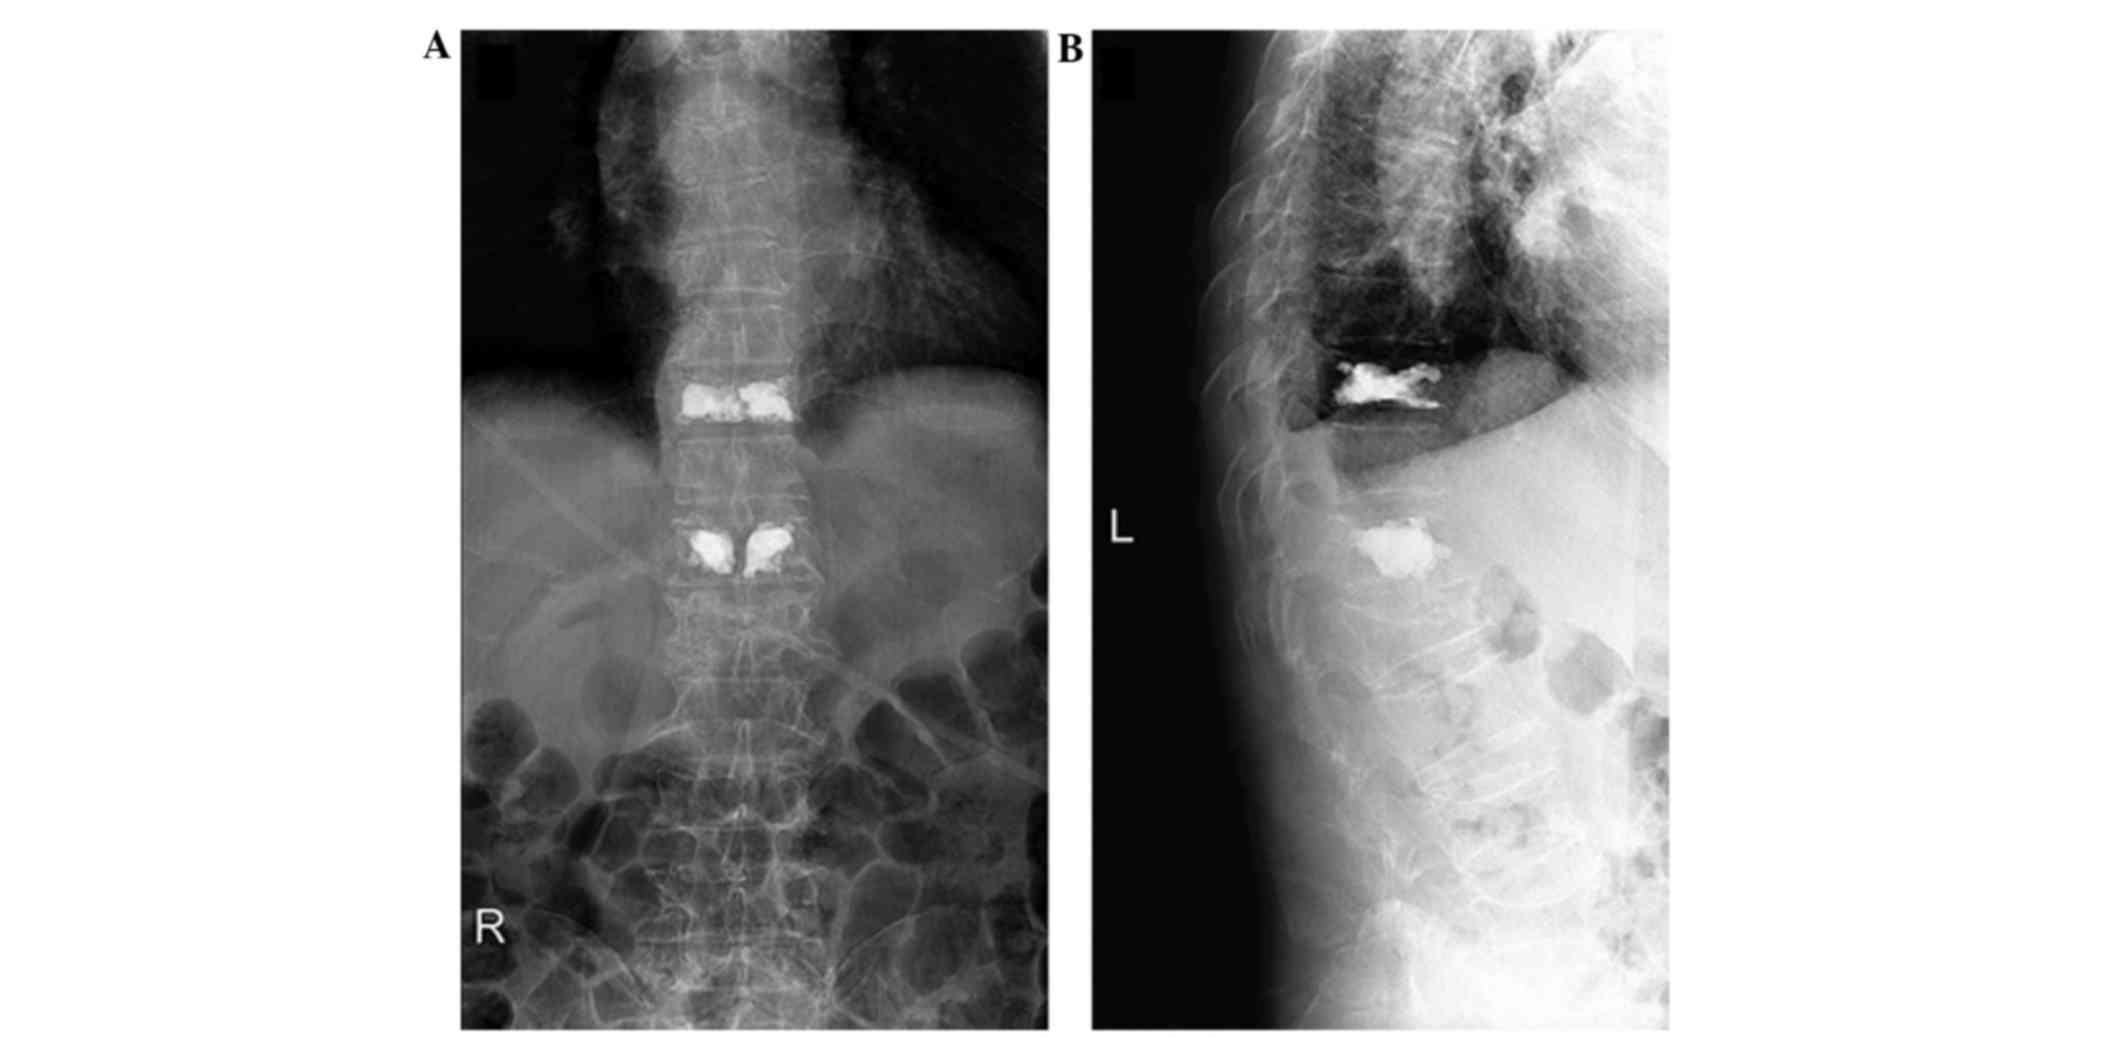

Case report

Figure 2.

Spinal computed tomography (CT) scan indicating multiple vertebral compression fractures, particularly in T10 and L1. (A) Coronal CT images showing severe osteoporosis and osteolytic, expansile lesions in T11. (B) Sagittal CT images showing multiple severe vertebrae fractures and cortical bone thinning.